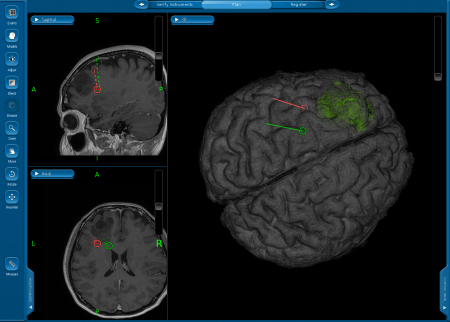

รศ.นพ.กฤษณพันธ์ บุณยะรัตเวช ศัลยแพทย์เฉพาะทางด้านประสาทศัลยศาสตร์ โรงพยาบาลจุฬาลงกรณ์ สภากาชาดไทย อธิบายถึงความแตกต่างของการผ่าตัดสมองแบบผู้ป่วยตื่น(Awake Craniotomy) และการผ่าตัดสมองโดยทั่วไปว่า การผ่าตัดสมองโดยทั่วไปผู้ป่วยจะไม่รู้สึกตัวจนกระทั่งการผ่าตัดเสร็จสิ้นทุกกระบวนการ แต่การผ่าตัดสมองแบบผู้ป่วยตื่นนั้น ผู้ป่วยจะถูกปลุกให้ตื่นขึ้นมาในช่วงหนึ่งของการผ่าตัดเพื่อให้แพทย์สามารถตรวจสอบการตอบสนองของผู้ป่วย เช่น การพูด การขยับแขนหรือขา การเปิด-ปิดตา และการรับรู้ความรู้สึก ฯลฯ เพื่อให้แน่ใจว่าการผ่าตัดสมองนั้นไม่ได้กระทบสมองส่วนอื่นๆที่สำคัญของผู้ป่วย การผ่าตัดรูปแบบนี้เป็นเทคนิคการผ่าตัดที่ใช้สำหรับผ่าตัดเนื้องอกในสมองหรือการผ่าตัดฝังเครื่องกระตุ้นสมอง ซึ่งบริเวณสมองส่วนที่ผ่าตัดนั้นจะอยู่ใกลกับสมองส่วนทีมี่ความสำคัญ เช่น เป็นสมองส่วนควบคุมการพูด การเคลื่อนไหวแขน ขา การกลอกตา การรับรู้ความรู้สึก เป็นต้น

หลังจากที่แพทย์อธิบายให้ผู้ป่วยเข้าใจถึงกระบวนการทดสอบแล้ว เมื่อถึงเวลาผ่าตัด วิสัญญีแพทย์จะให้ยานอนหลับและยาแก้ปวดแก่ผู้ป่วย ซึ่งในช่วงที่ผู้ป่วยนอนหลับนั้นเป็นช่วงเวลาสำคัญที่วิสัญญีแพทย์จะต้องดูแลระบบหายใจและระบบไหลเวียนเลือดให้เกิดความปลอดภัย อาจต้องมีการใส่อุปกรณ์เปิดทางเดินหายใจเพื่อให้ผู้ป่วยสามารถหายใจเข้า–ออกได้อย่างสะดวก ฉีดยาชาที่บริเวณหนังศีรษะเพื่อลดความเจ็บปวดขณะตื่น ศัลยแพทย์จะใส่หมุดตรึงศีรษะเพื่อให้ผู้ป่วยอยู่ในตำแหน่งที่สามารถผ่าตัดได้อย่างสะดวก และใส่สายสวนปัสสาวะเพราะการผ่าตัดอาจยาวนานและอาจต้องให้ยาขับปัสสาวะเพื่อลดอาการสมองบวม จากนั้นศัลยแพทย์จึงเริ่มทำการผ่าตัดสมอง

รศ.นพ.กฤษณพันธ์ กล่าวสรุปถึงประโยชน์ของการผ่าตัดสมองแบบผู้ป่วยตื่น (Awake Craniotomy) ว่า เป็นการผ่าตัดที่มีประโยชน์อย่างยิ่งเนื่องจากการผ่าตัดด้วยวิธีนี้ช่วยให้ศัลยแพทย์สามารถผ่าตัดรักษาในกลุ่มโรคที่มีอาการอยู่ใกล้กับสมองส่วนที่มีความสำคัญได้เป็นอย่างดี อีกทั้งยังเป็นการรักษาที่มีประสิทธิภาพมาก เพราะในระหว่างการผ่าตัด แพทย์สามารถให้การรักษาผู้ป่วยได้อย่างเต็มที่ที่สุดและเห็นการตอบสนองของผู้ป่วยได้อย่างชัดเจน นอกจากนี้การผ่าตัดสมองแบบผู้ป่วยตื่นจะสำเร็จลุล่วงไม่ได้เลย หากขาดการประสานงานที่ลงตัวระหว่างศัลยแพทย์และวิสัญญีแพทย์ ที่ต้องทำให้ผู้ป่วยหลับและตื่นขึ้นมาเพื่อทำการทดสอบการตอบสนองต่างๆ ให้เป็นไปอย่างราบรื่นที่สุด ที่ผ่านมาโรงพยาบาลจุฬาลงกรณ์สามารถให้การผ่าตัดรักษาผู้ป่วยด้วยวิธีการนี้สำเร็จไปแล้วกว่า 80 ราย ซึ่งในอนาคตทีมแพทย์โรงพยาบาลจุฬาลงกรณ์จะพัฒนาการผ่าตัดสมองแบบผู้ป่วยตื่นให้มีประสิทธิภาพมากยิ่งขึ้นเพื่อช่วยให้ผู้ป่วยกลับมามีคุณภาพชีวิตที่ดีขึ้นได้ต่อไป